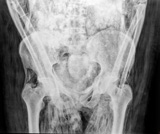

4.

ミイラ(骨盤) Mummy image (pelvis)

この古代エジプトのミイラの骨盤は,CSHの新しいCRシステムで撮影された。X線画像は広く,そして浅い坐骨切痕,恥骨結合と広い恥骨下角を写しており,このミイラが30から40歳の女性ものであることを示している。高吸収域の腹腔内には,内臓と砂あるいは塩が入った袋が詰められており,おそらく内臓を入れる壷(canopic jar)に入れて保存するより,むしろ内臓をミイラ内に戻す方を選択したものと考えられる。この手法も当時しばしば行われた。

撮影および画像提供: フィールド博物館 |